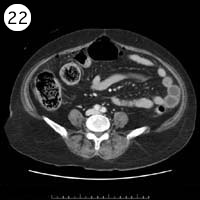

57歳 女性

単純CT

造影CT